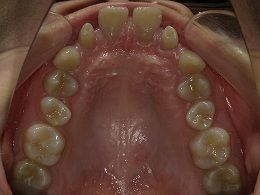

治療前上顎

治療中上顎

治療後上顎

お試し矯正後、深い噛み合わせ改善のため上下全体矯正中の患者様の症例になります。